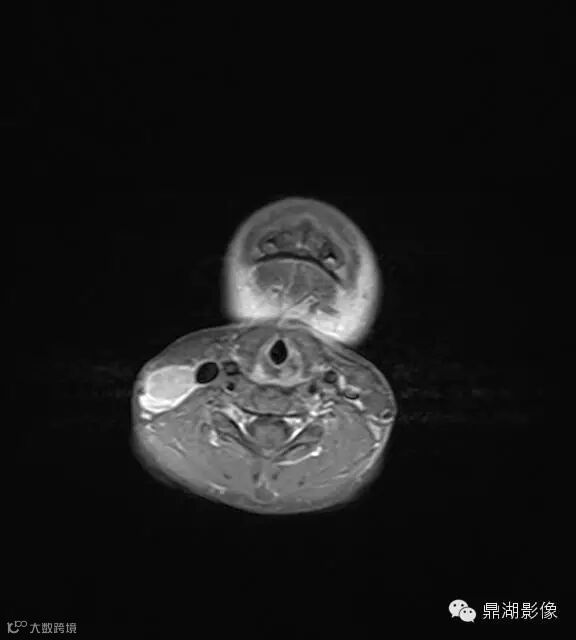

上海儿童医院韩燕乔教授诊断:考虑淋巴结炎 ,可见杯状分层,液液平

神经源性肿瘤:肿块较大,信号常不均,有人认为肿瘤位于屈肌的区域或伴有肌肉萎缩强烈提示神经源性肿瘤。

淋巴结核:多融合成团,呈花环状,边缘强化,淋巴结内见到斑点状钙化有助结核的诊断。

猫抓病性淋巴结炎:不少医生诊断为猫爪病,该病确实很接近。均为炎性改变,脓肿、坏死形成时,虽呈边缘强化特点,但多个淋巴结间界限清楚,无融合改变,内也无斑点状钙化。